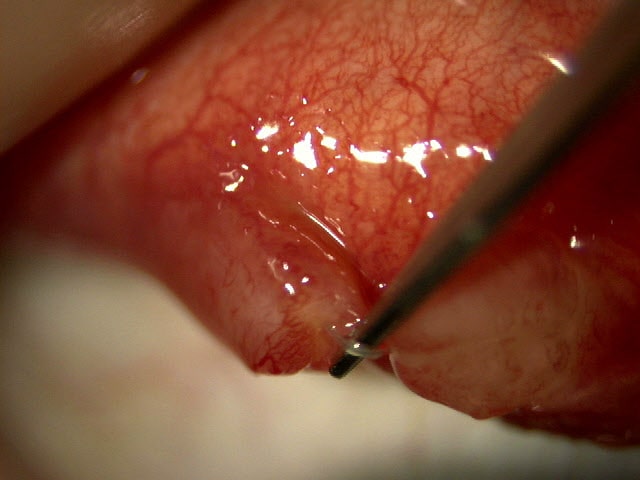

重瞼縫合糸露出による巨大不良肉芽

3年前に埋没重瞼手術。異物感にて眼科受診し春季カタルとしてタクロリムス点眼にて経過観察されていた。改善なく当院に受診。 右眼 左眼 上皮障害はみられない。 巨大な不良肉芽があり先端から縫合糸がでている 巨大な不良肉芽があり先端から縫合糸がでて...